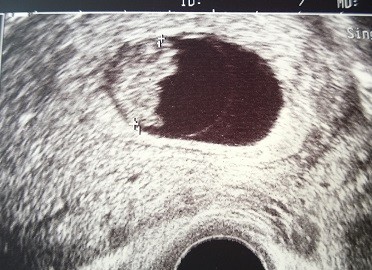

Maleństwo miało 11mm, serducho jak dzwon, dużo wód płodowych no i dostałam skierowanie na prenatalne do Żor

Będę robić tylko USG, na badania inwazyjne się nie zgodzę, boję się okropnie.. Czuję się wspaniale, żadnych dolegliwości oprócz odrzucenia niektórych potraw i jem o wiele mniej, ale częściej